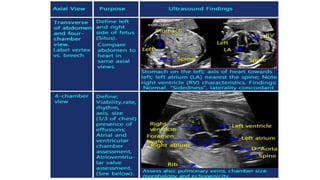

• #16 Heart Position and Axis. Normal position and axis of the heart. The heart is predominantly in the left side of the chest, with the apex of the heart pointing leftward. Dual-screen image shows the stomach also on the left side.

• #17 Schematic drawing and apical four-chamber view (B) with a highlight of the left ventricle (LV) (C) and right ventricle (RV) (D) in a normal fetus, showing the differentiating features of the LV and RV. The LV is longer than the RV (double-sided arrows), is smooth, and forms the apex of the heart (yellow arrow). The RV is coarse and has the typical moderator band (white arrow) in its apex. The tricuspid valve (TV) is shown to insert more apically on the septum than the mitral valve (MV).